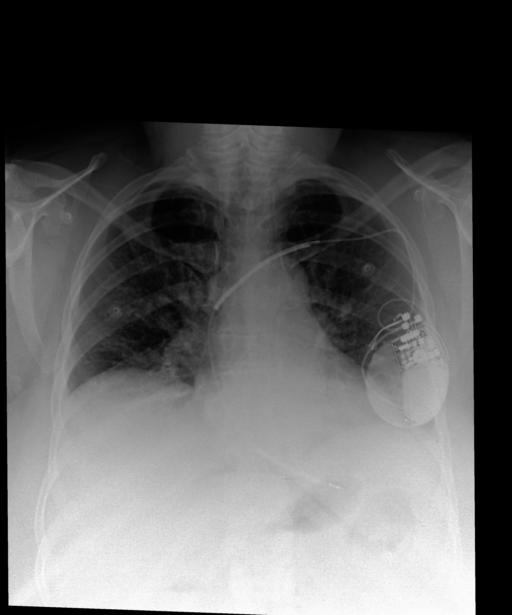

Figures 3 and 4 show success cases from MAIRA-1. In Figure 3, MAIRA-1 successfully avoids hallucinating a comparison to a prior study (‘Lung volumes are low.’), while Figure 4 shows examples of such hallucination (‘… pulmonary edema, new compared to the prior study.’), with other details largely correct.

Refer to caption

Original report

INDICATION: _F with shortness of breath, congestive heart failure.

FINDINGS: Lung volumes are low compared to the previous study. Left-sided AICD device is noted with single lead terminating in unchanged position in the right ventricle. Heart size appears at least mildly enlarged. The mediastinal and hilar contours are unremarkable. There is crowding of the bronchovascular structures without overt pulmonary edema. Streaky opacities in the lung bases likely reflect areas of atelectasis. No pleural effusion or pneumothorax is present. There are no acute osseous abnormalities.

MAIRA-1

FINDINGS: Lung volumes are low. Left-sided AICD device is noted with single lead terminating in the region of the right ventricle. Heart size is mildly enlarged. Mediastinal and hilar contours are unremarkable. Crowding of bronchovascular structures is present without overt pulmonary edema. Patchy opacities in the lung bases likely reflect areas of atelectasis. No pleural effusion or pneumothorax is present. There are no acute osseous abnormalities.

Figure 3: MAIRA-1 generates the Findings section for a more complex case with multiple findings. Here, the original report describes the lung volumes in relation to a prior image which is not available to MAIRA-1; in this case MAIRA-1 simply describes the lung volumes as low (highlighted). RadCliQ: 0.239.